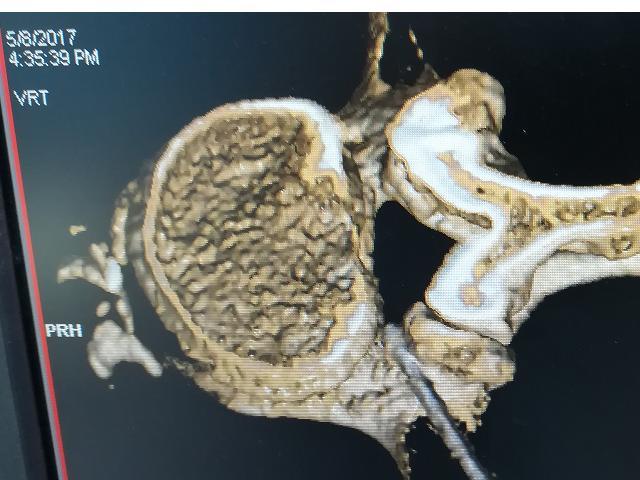

脊柱内镜翻修腰椎间盘突出症胶原酶溶核术后复

5092x2934 - 2124KB - JPEG

脊柱内镜翻修腰椎间盘突出症胶原酶溶核术后复

5194x2450 - 1506KB - JPEG

脊柱内镜翻修腰椎间盘突出症胶原酶溶核术后复

5312x3984 - 2972KB - JPEG

脊柱内镜翻修腰椎间盘突出症胶原酶溶核术后复

5310x2870 - 2720KB - JPEG

脊柱内镜翻修腰椎间盘突出症胶原酶溶核术后复

5312x3984 - 3474KB - JPEG

脊柱内镜翻修腰椎间盘突出症胶原酶溶核术后复

4340x3632 - 2061KB - JPEG

脊柱内镜翻修腰椎间盘突出症胶原酶溶核术后复

4002x3272 - 1704KB - JPEG